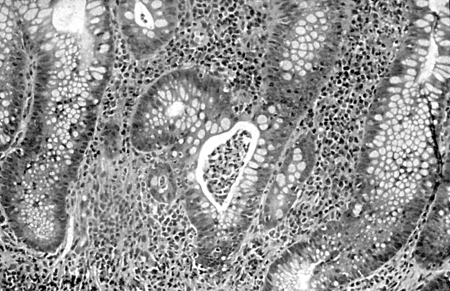

Ulcerative colitis

Colonic biopsy specimen showing severe mucosal inflammation, formation of crypt abscess, mild glandular atrophy, and distortion, suggesting an active phase of ulcerative colitis; haematoxylin/eosin staining, ×400 magnification

From Iannone F, Scioscia C, Musio A, et al Leucocytoclastic vasculitis as onset symptom of ulcerative colitis Ann Rheum Dis 2003 Aug;62(8):785-6; used with permission